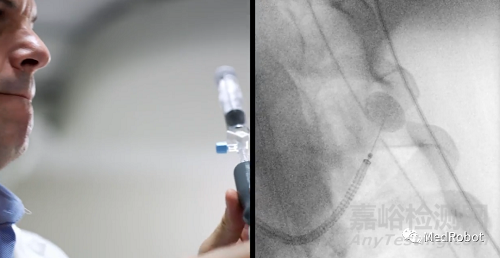

PlanPoint是Ion配備的一個(gè)軟件平臺(tái),可從筆記本電腦進(jìn)行訪問(wèn),醫(yī)生可以在進(jìn)入手術(shù)室之前使用它來(lái)制定機(jī)器人輔助支氣管鏡導(dǎo)航和活檢的策略。它使用病人肺部的CT掃描來(lái)生成3D氣道樹(shù)。一旦你識(shí)別出一個(gè)有針對(duì)性的肺結(jié)節(jié),Ion的PlanPoint軟件會(huì)自動(dòng)創(chuàng)建往結(jié)節(jié)的路徑。

Ion的超細(xì)機(jī)械導(dǎo)管和先進(jìn)的可操作性使導(dǎo)航遠(yuǎn)至周圍的肺部,其2.0毫米工作通道和3.5毫米外徑導(dǎo)管可以穿過(guò)難以導(dǎo)航的小氣道到達(dá)肺的所有18個(gè)部位。Ion系統(tǒng)的外圍視覺(jué)探針可在導(dǎo)航期間提供直接視覺(jué),光纖傳感技術(shù)讓醫(yī)生可以隨時(shí)準(zhǔn)確了解導(dǎo)管的精確位置和形狀信息且不易受到干擾。